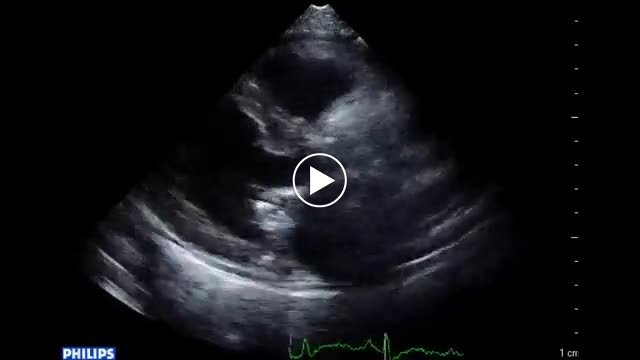

• 図7 僧帽弁輪石灰化(MAC)によるMS(degenerative MS患者、大動脈弁狭窄症合併例) b